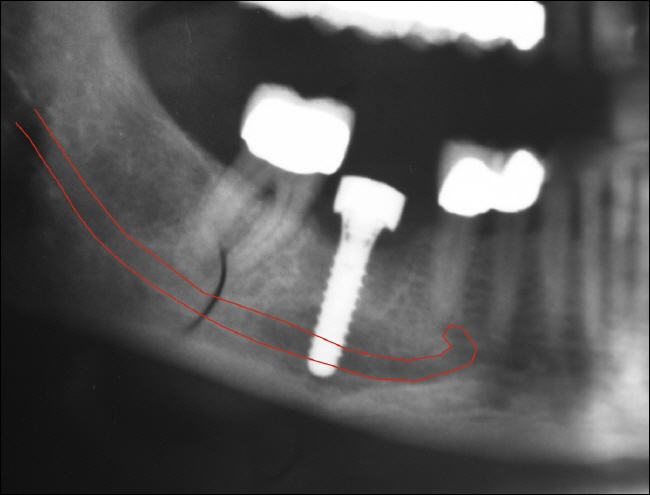

Im hinteren bzw. seitlichen Unterkieferknochen verläuft ein sehr sensibler Nerv (sensibel=Nerv, der für die Gefühlsempfindung zuständig ist), welcher die untere entsprechende Lippenseite mit Gefühl versorgt.

Bei der Implantation in Nervnähe kann es beispielsweise alleine schon durch das Abhalten der zu schützenden Strukturen zu einer vorübergehenden Reizung des Nervs kommen. Dies äußerst sich in aller Regel so, dass ein dumpfes oder taubes Gefühl in der Lippenregion ist, welches ein paar Tage bis Wochen anhalten kann. In einzelnen Fällen kann auch ein „kribbeliges“ Gefühl in der Lippe sein, also eine Gefühlsüberempfindung. Wird der Nerv beispielsweise durch zu tielfes bohren des Implantatlagers durchtrennt, so kann ein dauerhaft taubes Gefühl in der Lippe verbleiben.